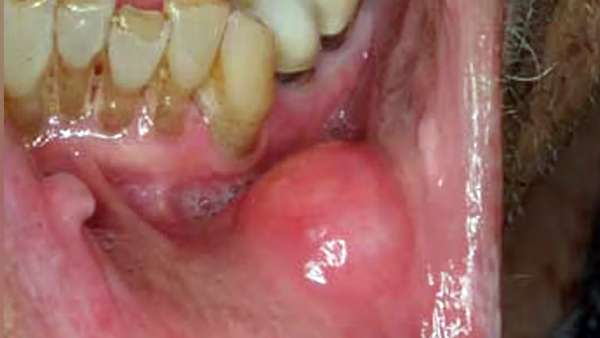

புற்று நோய் என்பதை ஆறாத புண் கட்டிகள் / வீக்கம், வலி, பசியின்மை, உதிரப்போக்கு, மலச்சிக்கல் போன்ற அறிகுறிகள் தொடர்ந்து இருந்தால் மருத்துவரை சந்தித்து அதன் பிறகு நோயை கண்டறிகிறோம். நோய் கண்டறியப்பட்ட சூழ்நிலையில் ஆரம்ப கட்டத்தில் இருந்தால் சிகிச்சை சிறப்பான பலனளித்து முழுவதுமாக நோயில் இருந்து மீளும் வாய்ப்பு அதிகமாக இருக்கும்.